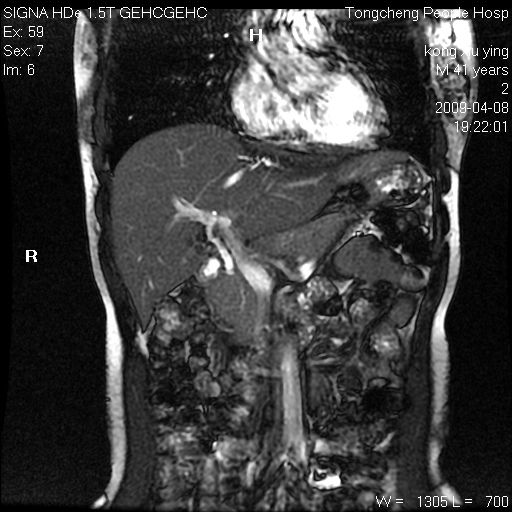

标题: CL1008:【经典】胆囊石榴籽样结石。

女,41岁。健康体检——彩超提示:胆囊显示不清。平素健康,无不适感。

腹部mr扫描及mrcp,图像如下: